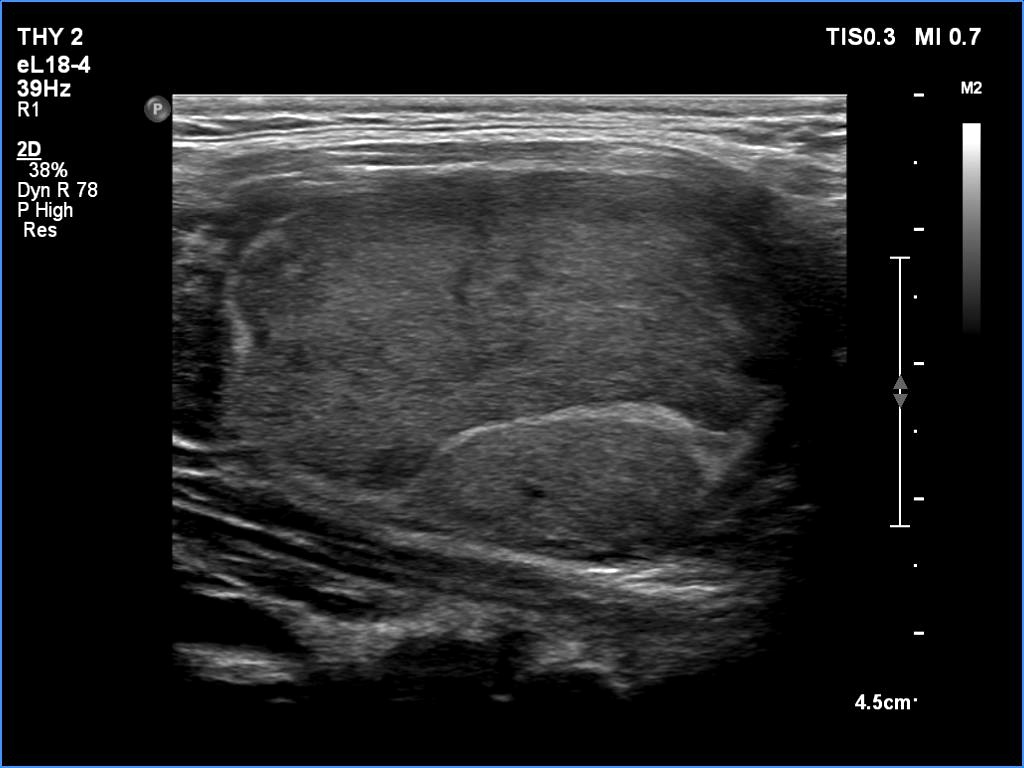

First examination (first row of images)

Clinical presentation: A 20-yr-old woman was referred for ultrasound examination. An elevated aTPO level was detected on evaluation of dysmenorrhea.

Palpation: Both lobes were firm. The left lobe was suspicious having a nodule.

Laboratory tests: TSH 2.08 mIU/L, FT4 13.2 pM/L, aTPO > 1300 U/mL.

The dimensions of the nodule in the left lobe were 18x17x22 mm, width, depth, length, respectively, the volume of the lesion was 3.5 mL.

The patient did not consent to aspiration cytology.